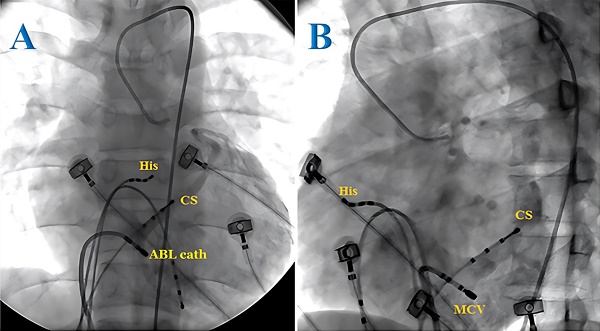

Radiofrequency catheter ablation for paroxysmal supraventricular tachycardia in children: Insights on its safety and efficacy from a lower middle-income country

Bui The Dung, Nguyen Minh Nhut, Luong Cao Son, Bui Gio An, Nguyen Minh Duc, Dang Van Phuoc

Int. J. Med. Sci. 2023; 20(10): 1293-1299. doi:10.7150/ijms.86594